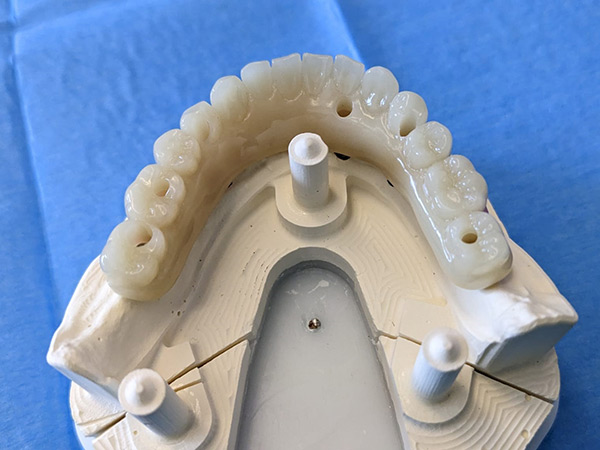

Sono state eseguite Tac con dima radiologica e progettazione per inserimento implantare tramite dima chirurgica di sei impianti AZ Implant tipo DX con overdenture a carico immediato.